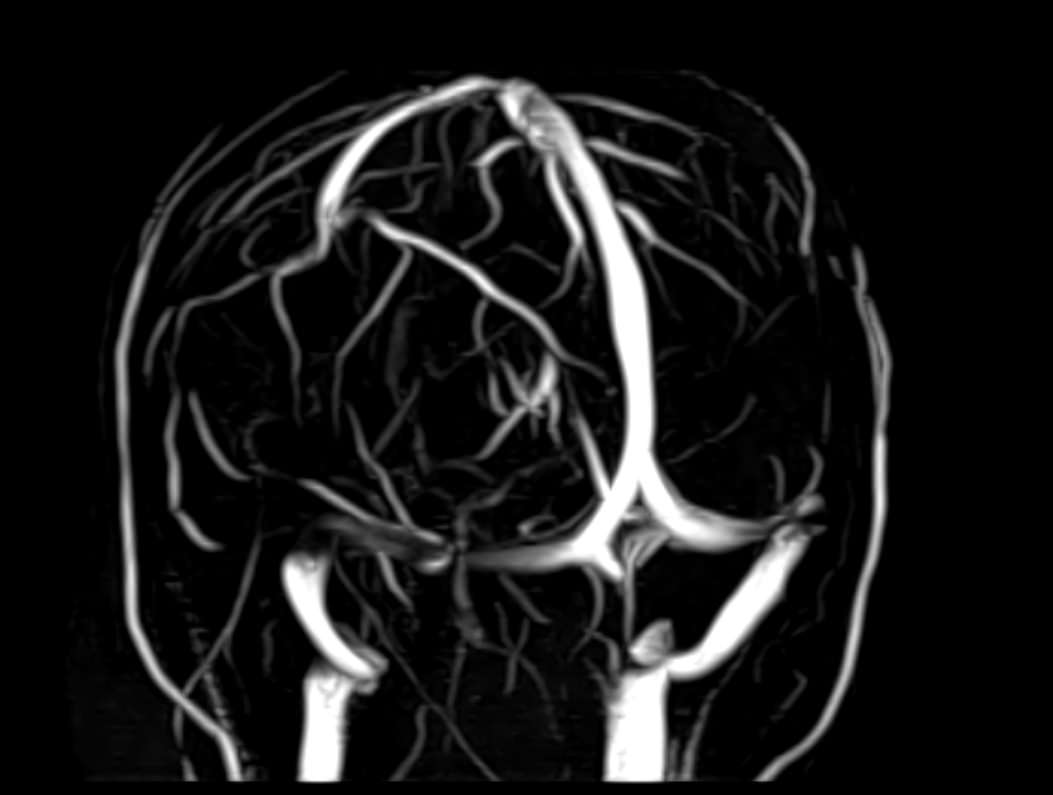

Стандартная МРТ головного мозга дает важную информацию о состоянии и структуре мозговой ткани для выявления большого числа заболеваний, в том числе опухолевых образований, демиелинизирующих заболеваний, воспалительных процессов головного мозга и мозговых оболочек. Стандартную МРТ головного мозга дополняет МР-ангиография, которая отображает состояние артериальной системы кровоснабжения головного мозга. МР-венография головного мозга позволяет детально изучить особенности анатомического и функциональной состояния венозного русла головного мозга.

Компьютерная программа обрабатывает данные, полученные при сканировании, и формирует объемные изображения как самого мозга, так и сосудистой системы в отдельности без прилегающих тканей. Обе методики применяются одновременно и взаимодополняют друг друга, давая полную диагностическую картину.